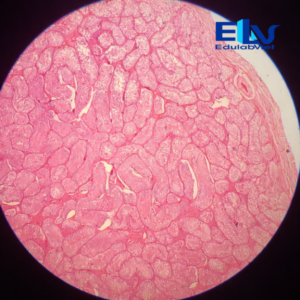

Tiêu bản tinh hoàn thỏ cắt ngang là mẫu tiêu bản hiển vi cố định thể hiện rõ cấu trúc vi thể của tinh hoàn, đặc biệt là các ống sinh tinh và các giai đoạn phát triển của tế bào sinh tinh. Sản phẩm phù hợp cho giảng dạy và thực hành môn Sinh học, Giải phẫu học, Mô học động vật.

Cấu trúc mô rõ ràng:

Quan sát rõ các ống sinh tinh, tế bào sinh tinh ở nhiều giai đoạn phát triển và mô kẽ tinh hoàn. -

Màu nhuộm đẹp – độ tương phản cao:

Tế bào được nhuộm đậm, sắc nét, giúp dễ dàng quan sát dưới kính hiển vi quang học. -